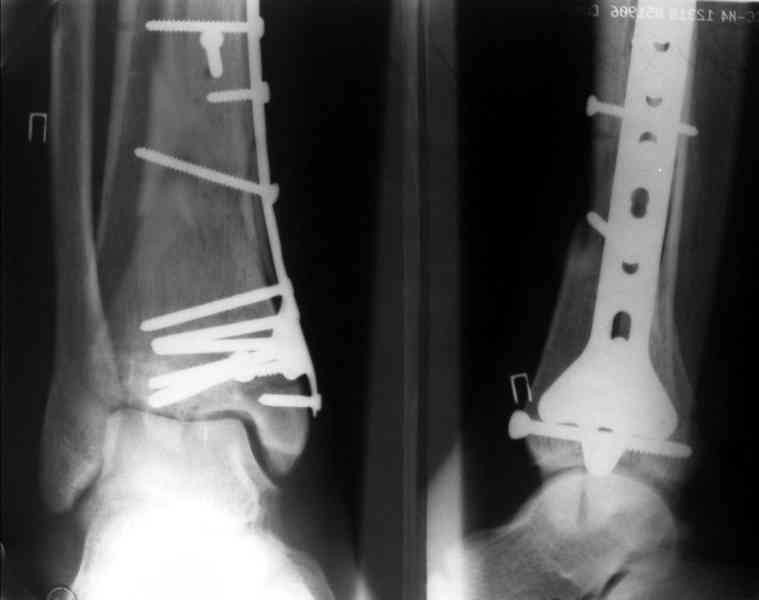

Кстати, при переломах переднего края по классификации АО В-3 при переломах пилона пластина укладывается по передней поверхности. Она достаточно тонкая и эластичная, не надо этого бояться. Посылаю три снимка.